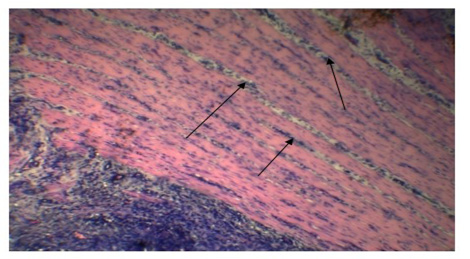

Inflammatory cells in the submucosa (Arrows). (H&E x 10).